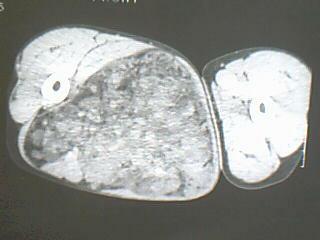

患者 男 34岁 右腿肿物。98年右侧外伤致股骨骨折,手术治疗,2001年二次手术(取钢板),发现大腿内侧有鸡蛋大小样肿块,无明显疼痛不适,2007年开始发现肿物明显增大,无发烧,无红肿。

右侧大腿内侧肌间含脂性巨块,密度不均,内见软组织成分及条管状钙化,错构瘤伴出血?真性或假性脂肪瘤

考虑右大腿内后方软组织内脂肪肉瘤可能性大。

右大腿内后方软组织内脂肪肉瘤可能性大。